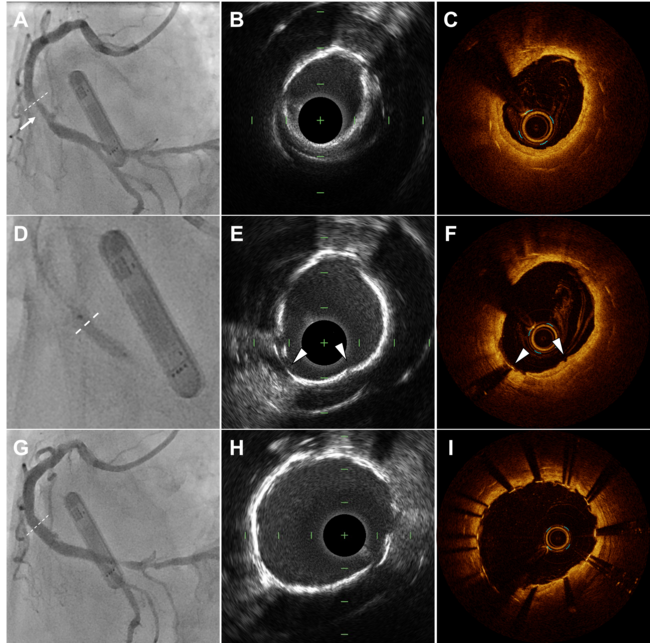

An 80-year-old man with a history of acute inferior myocardial infarction was admitted to our hospital. He had undergone bare-metal stent (3.5/28 mm) implantation in the mid-right coronary artery 22 years prior. Drug-induced myocardial perfusion imaging revealed perfusion defects in the peri-infarction lesion, accompanied by left ventricular hypokinesis during stress. Coronary angiography demonstrated in-stent restenosis (ISR) in the distal segment of the stent (Figure A). Given these findings, we planned revascularization for this ISR lesion.

Intravascular ultrasound (IVUS) AltaView, Terumo) revealed neointima with a circumferential high-intensity surface, suggesting calcified neoatherosclerosis (Figure B). Optical coherence tomography (OCT) (Dragonfly OpStar, Abbott) further confirmed the presence of circumferential calcified plaque with a maximum thickness of 200 µm (Figure C, Video 1). With the aim of creating fractures in this calcified neointima to achieve luminal gain, we performed intravascular lithotripsy (IVL) (Shockwave C2 3.5/12 mm; Shockwave Medical) (Figure D). Subsequent IVUS and OCT showed the formation of multiple cracks within the calcified plaque (Figure E and F, Video 2). Finally, a new everolimus-eluting stent (4.5/20 mm) successfully dilated the lesion (Figure G-I, Video 3). The procedure was completed without complications, and the patient has remained free of symptoms since the intervention.